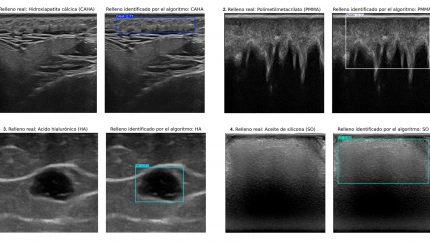

El nuevo sistema, basado en aprendizaje profundo, resuelve este problema al discriminar automáticamente entre hidroxiapatita cálcica, ácido hialurónico, polimetilmetacrilato y aceite de silicona. El equipo ha sido dirigido por la doctora Ximena Worstman de la Universidad de Chile, con la participación clave de los profesores Manuel Lozano y Francisco J. Rodríguez de la Universidad de Granada.

Para el entrenamiento del algoritmo se ha contado con la participación de especialistas en dermatología en un contexto multicentro internacional. Además, se han utilizado equipos ecográficos de diversa complejidad, desde unidades portátiles hasta dispositivos de alta gama, para garantizar la adaptabilidad del sistema a diferentes entornos clínicos.